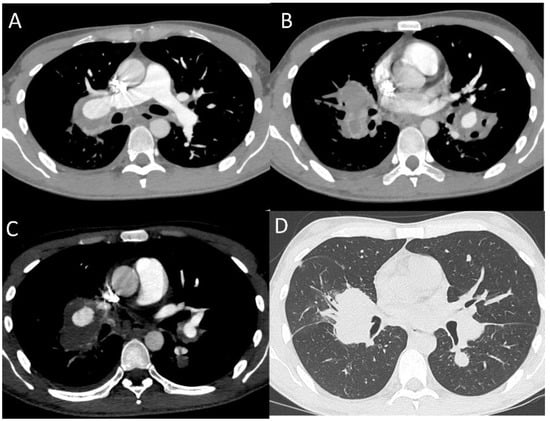

2.1.2. Pulmonary Arterial Manifestations

- Iula, G.; Ziviello, R.; del Vecchio, W. Aneurysms of Proximal Pulmonary Arteries: CT Diagnosis and Preoperative Assessment. Eur. Radiol. 1996, 6, 730–733. [Google Scholar] [CrossRef] [PubMed]

- Cil, B.E.; Turkbey, B.; Canyiǧit, M.; Kumbasar, O.O.; Celik, G.; Demirkazik, F.B. Transformation of a Ruptured Giant Pulmonary Artery Aneurysm into an Air Cavity after Transcatheter Embolization in a Behçet’s Patient. Cardiovasc. Intervent. Radiol. 2006, 29, 151–154. [Google Scholar] [CrossRef]

- Hamuryudan, V.; Er, T.; Seyahi, E.; Akman, C.; Tüzün, H.; Fresko, I.; Yurdakul, S.; Numan, F.; Yazici, H. Pulmonary Artery Aneurysms in Behçet Syndrome. Am. J. Med. 2004, 117, 867–870. [Google Scholar] [CrossRef]

- Cozzi, D.; Moroni, C.; Cavigli, E.; Bindi, A.; Bonini, M.C.; Fattorini, C.; Miele, V. Behçet Disease in Emergency Department: A Rare Case Presenting with Haemoptysis and Massive Pulmonary Arterial Aneurysms. Sarcoidosis. Vasc. Diffuse Lung Dis. 2021, 38, e2021014. [Google Scholar] [CrossRef]

- Emad, Y.; Ragab, Y.; Robinson, C.; Pankl, S.; Young, P.; Fabi, M.; Bawaskar, P.; Ibrahim, O.; Erkan, D.; Barman, B.; et al. Pulmonary Vasculitis in Hughes-Stovin Syndrome (HSS): A Reference Atlas and Computed Tomography Pulmonary Angiography Guide-a Report by the HSS International Study Group. Clin. Rheumatol. 2021, 3, 4993–5008. [Google Scholar] [CrossRef]

- Ayyildiz, V.; Aydin, Y.; Ogul, H. Pulmonary Artery Aneurysm Partially Regressing With Medical Treatment in Behçet’s Disease. Arch. Bronconeumol. 2021, 57, 588. [Google Scholar] [CrossRef]

- Seyahi, E.; Yazici, H. Behçet’s Syndrome: Pulmonary Vascular Disease. Curr. Opin. Rheumatol. 2015, 27, 18–23. [Google Scholar] [CrossRef]

- Eroglu, D.S.; Torgutalp, M.; Baysal, S.; Colaklar, A.; Sezer, S.; Yayla, M.E.; Uzun, C.; Turgay, T.M.; Kinikli, G.; Ates, A. Clinical Characteristics of Pulmonary Artery Involvement in Patients with Behçet’s Syndrome: Single-Centre Experience of 61 Patients. Clin. Rheumatol. 2021, 40, 4127–4134. [Google Scholar] [CrossRef] [PubMed]